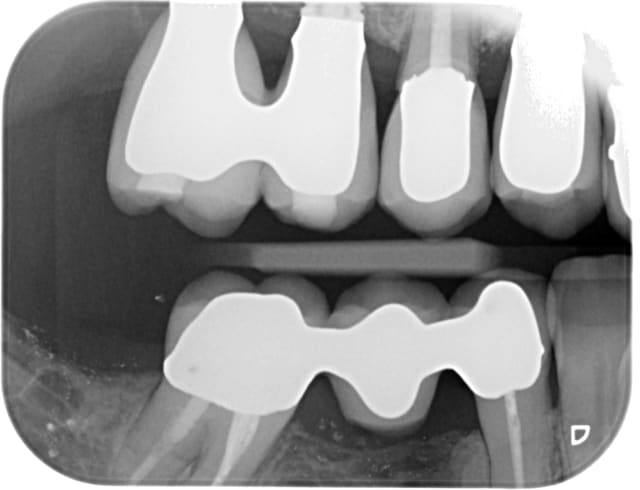

Photo des moulages de face en occlusion ?

Pas encore réfléchi mais ça m a bien l air occlusal ton affaire.....

Tiens mon lapin!